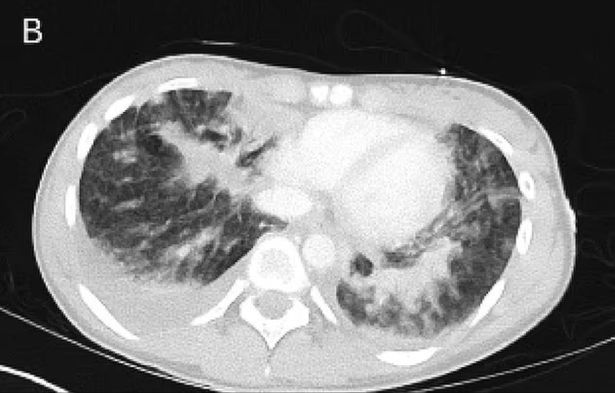

Powodem było nagromadzenie płynu w płucach - było go na tyle dużo, że groziło jej "utonięcie". Lekarze od razu przenieśli ją na oddział intensywnej terapii, gdzie została podłączona do tlenu. Niestety, nie wiedzieli, co mogło doprowadzić do takiego stanu.

Po kilku dniach stan nastolatki się ustabilizował na tyle, że lekarze postanowili wykonać jej szczegółowe badania płuc. Patrząc na wyniki, stwierdzili, że nastolatka cierpi na stosunkowo nową chorobę o nazwie EVALI, która została po raz pierwszy opisana w 2019 roku. Jest to uszkodzenie płuc związane z używaniem e-papierosów lub waporyzatorów, zawierających tetrahydrokannabinol (THC) i octan witaminy E.